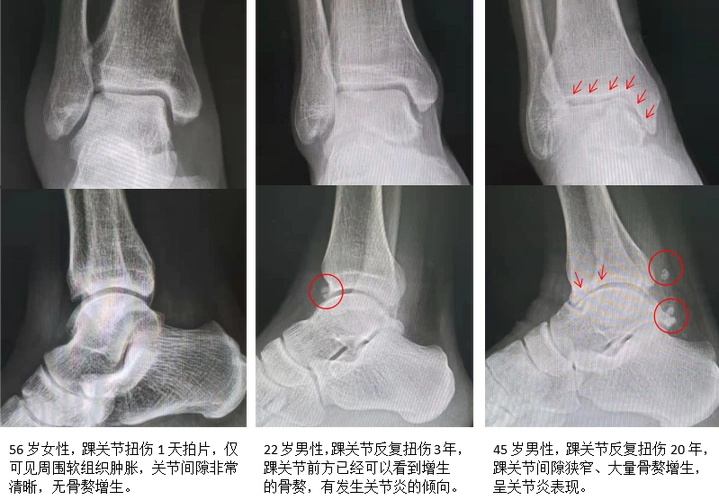

慢性崴脚在悄悄的破坏你的踝关节_踝部扭伤_介绍_治疗方式_日常注意